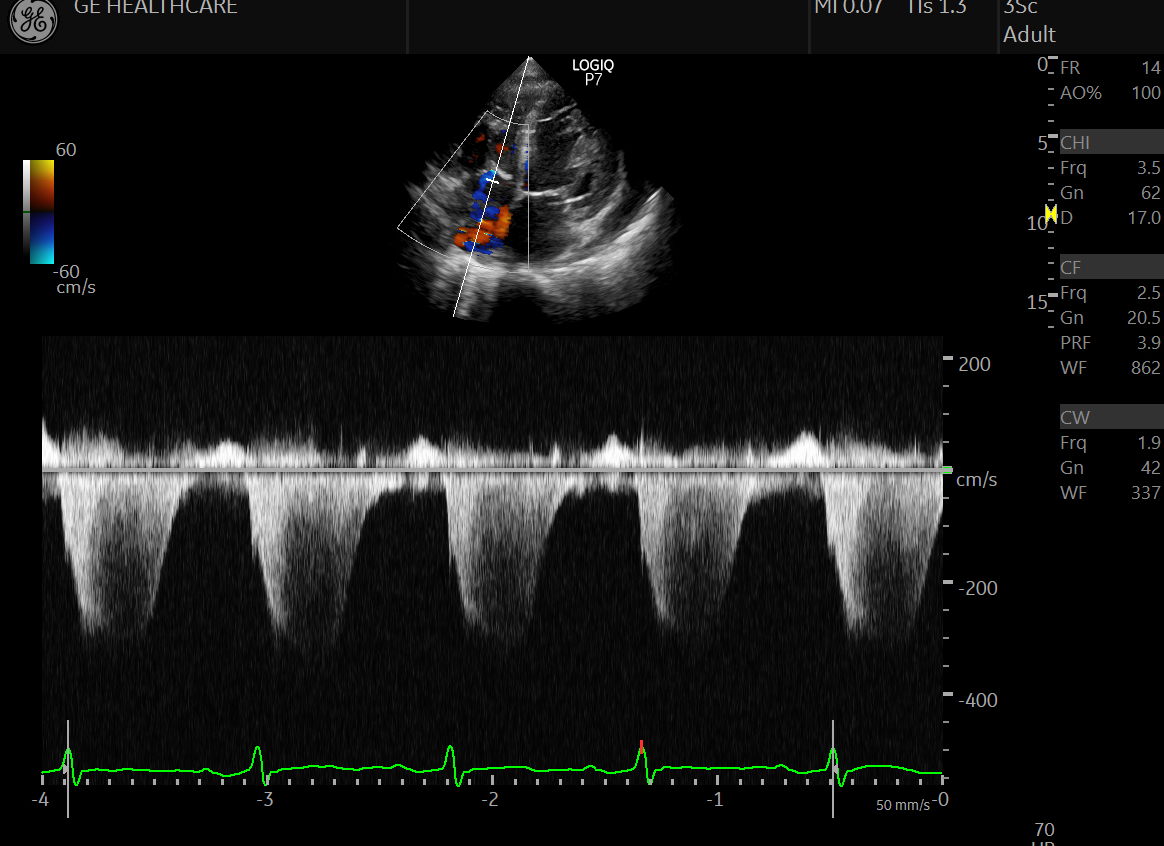

심장 초음파는 초음파를 이용하여 실시간으로 심장의 움직이는 모습을 관찰할 수 있으며, 심장의 해부학적 구조의 이상, 심장 기능, 심장 내 압력 등을 실시간으로, 비침습적으로 관찰할 수 있는 검사법입니다.

경흉부 심초음파, 경식도 심초음파, 운동 부하 심초음파, 도부타민 부하 심초음파, 어고노빈 부하 심초음파, 심근조영 심초음파, 삼차원 심초음파 등 몇 가지 형태로 구분하여 시행됩니다.